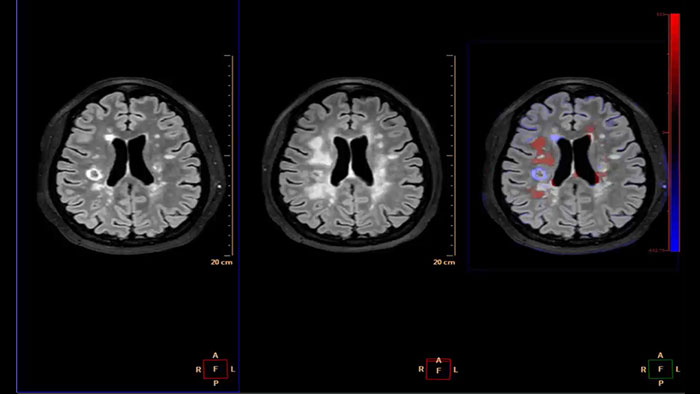

Computed diffusion weighted images at a b-value of choice

The application is intended to view, process and analyze MRI Diffusion Weighted Images. It calculates and displays cDWI at a

b-value of choice (from 0 to 5,000 s/mm2) and provides advanced supportive analysis and visualization tools of diffusion MRI images and parametric maps.

Analyze diffusion and anisotropic properties of tissue

Designed to analyze diffusion and anisotropic properties of tissue. The application evaluates DWI series to generate parametric maps such as ADC and eADC. For Diffusion Tensor Imaging data, additional parametric maps are generated, including fractional anisotropy, axial diffusivity or radial diffusivity.

Benefits